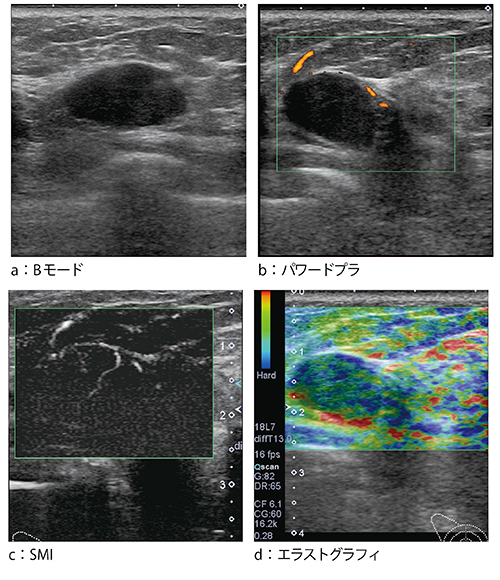

●症例2:線維腺腫(39歳)

症例2は,超音波検診で右乳房に比較的境界明瞭な腫瘤性病変が指摘された(図4 a)。パワードプラでは,腫瘤の周囲に血流が点在する様子が認められるが,内部の血流は不明瞭であった(図4 b)。しかし,SMIでは周囲の血流に加え,腫瘤内を貫くような血流が認められた(図4 c)。エラストグラフィでは,軟らかい腫瘤として描出され(図4 d),最終的には針生検にて線維腺腫と診断された。

図4 症例2:線維腺腫(39歳)